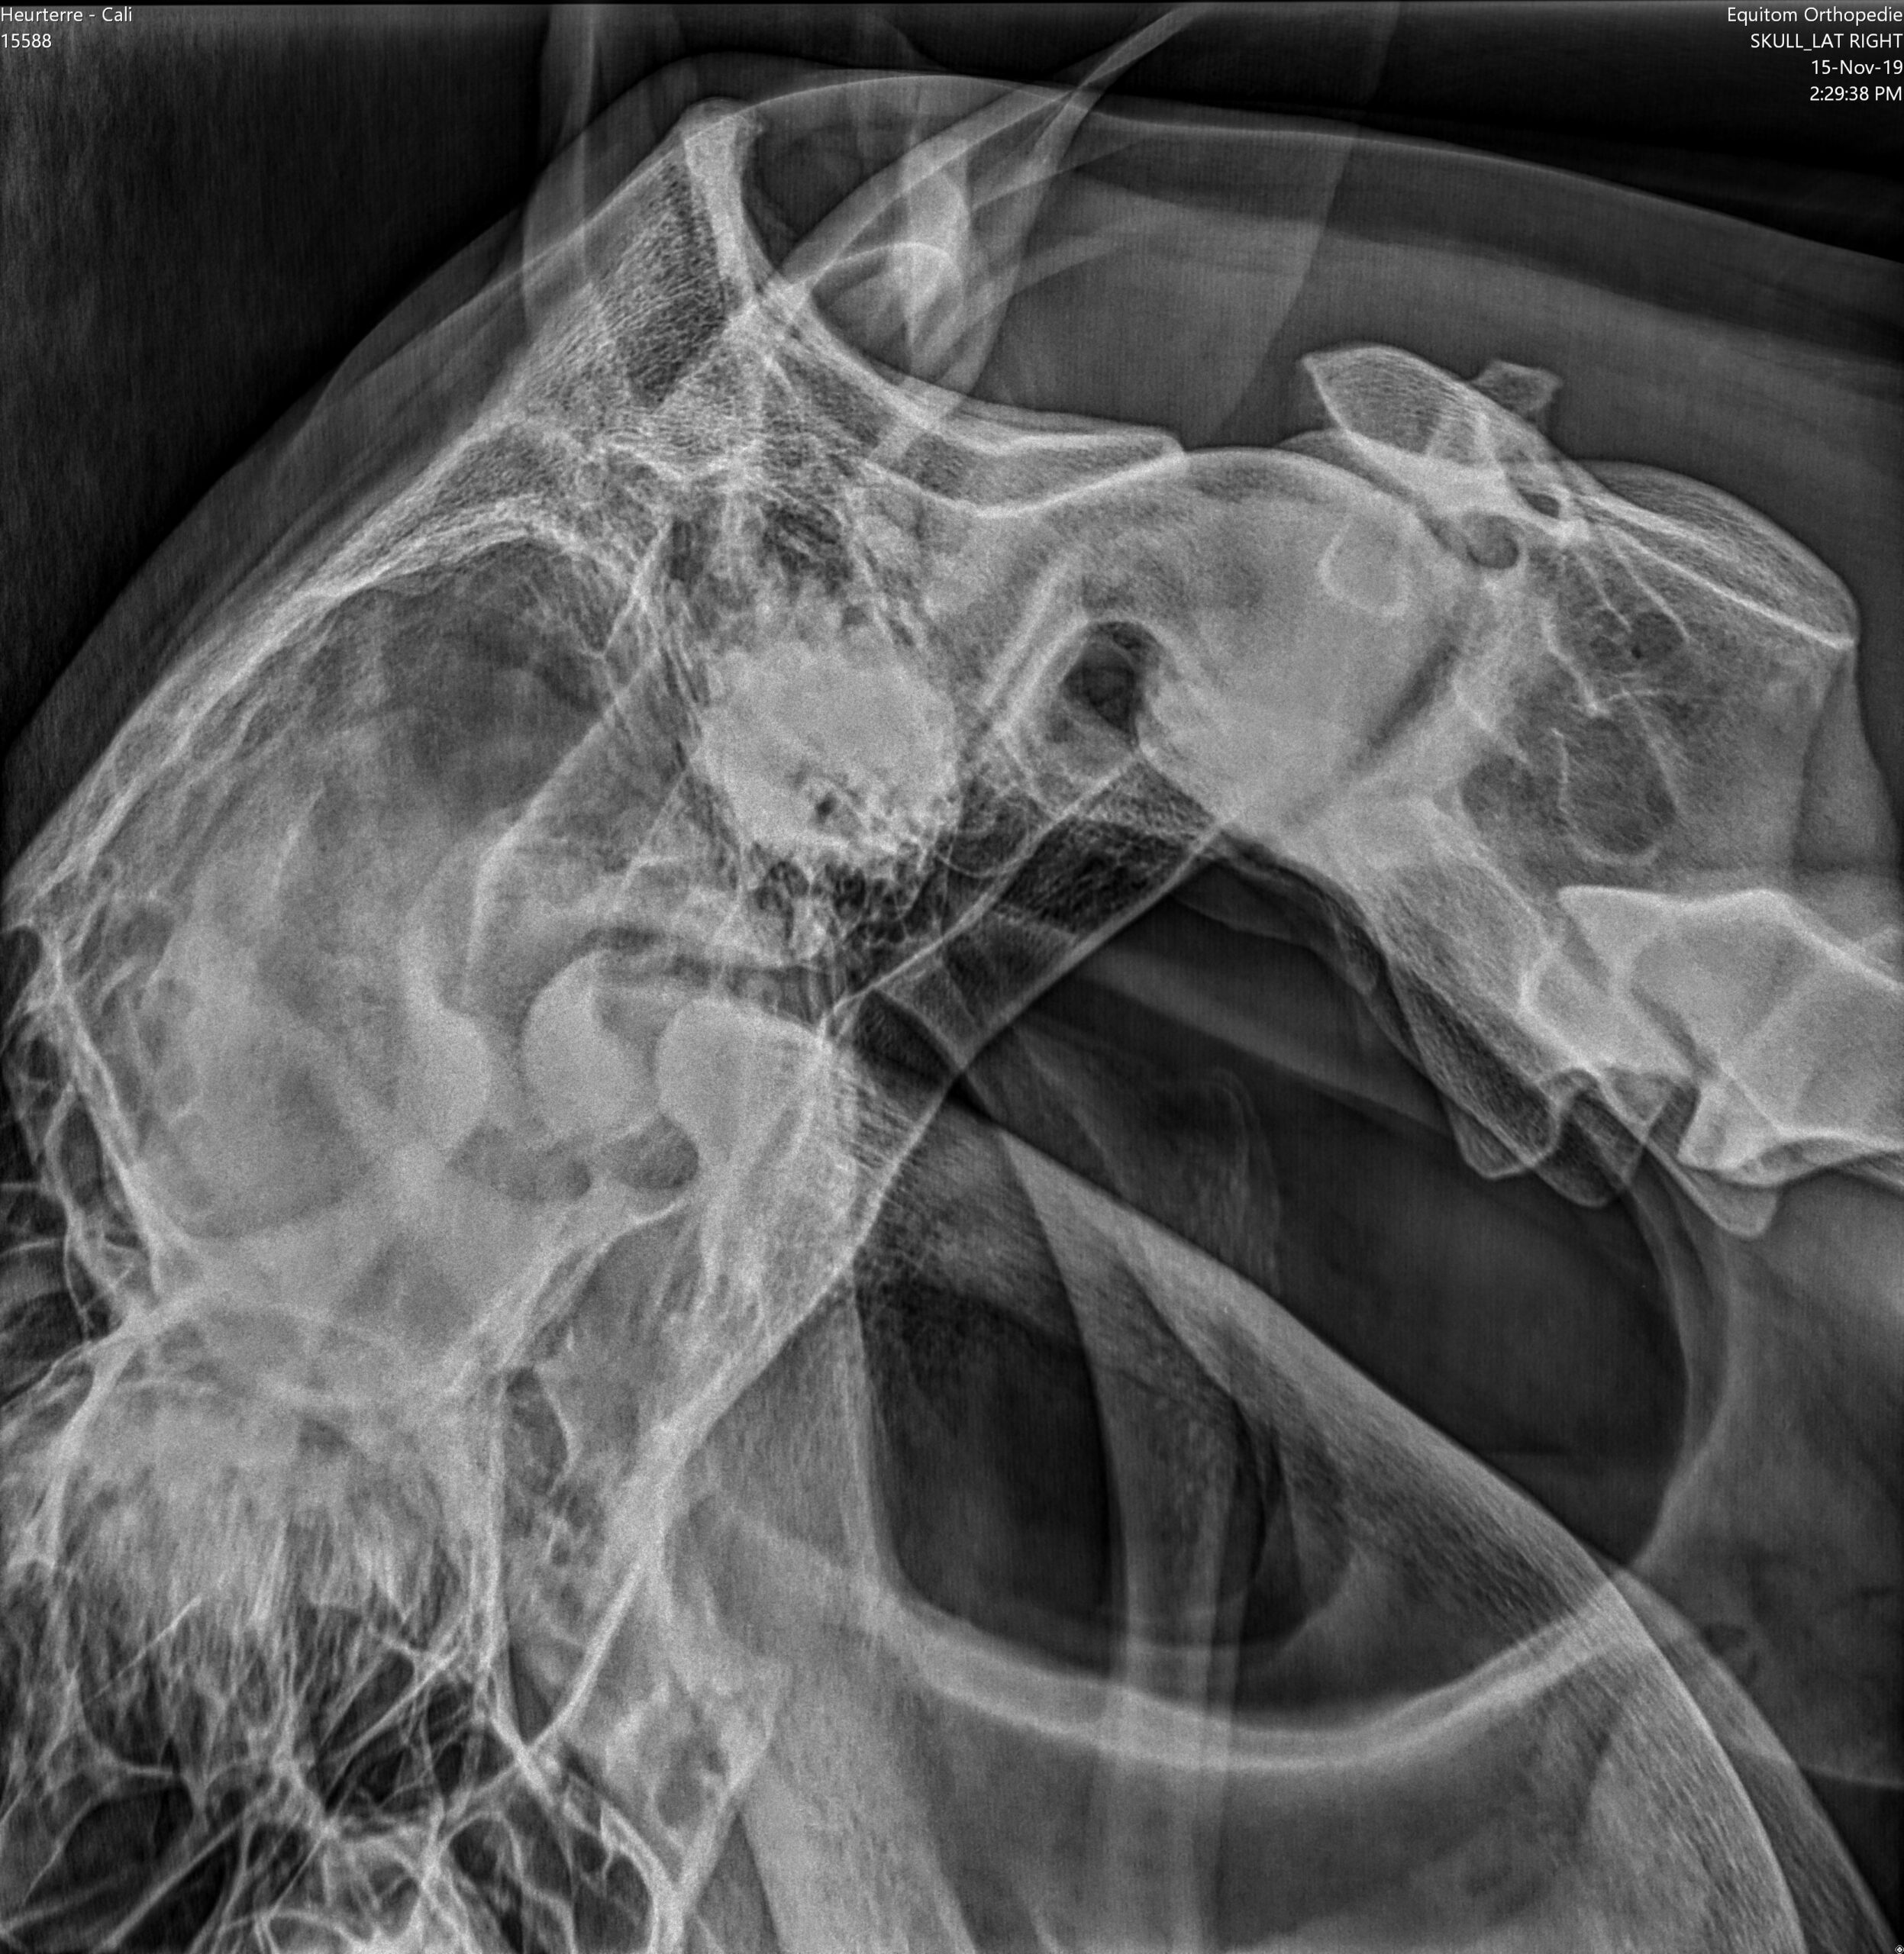

Každý kůň má dva vzdušné vaky, které leží po stranách hrdla. Jsou to pytlovité výchlipky Eustachovy trubice, která propojuje hrdlo a ucho koně. Vaky jsou naplněny vzduchem a jsou jasně viditelné na rentgenových snímcích jako tmavé plochy (obr. 1). Jejich funkce stále není zcela objasněná, ale je jisté, že kolem nich nebo přímo skrz ně vedou velmi důležité struktury.

Některé z hlavních cév zásobujících hlavu se nacházejí v těsné blízkosti stěn vzdušných vaků. Jedná se zejména o hlavní tepnu (krkavici), která vystupuje přímo ze srdce a zásobuje kyslíkem hlavu a mozek. Na úrovni hlavy se tato tepna rozdělí do několika silných tepenných větví, které procházejí stěnami vzdušných vaků (vnější a vnitřní větev krkavice a čelistní tepna, obr. 2).

Hlavové nervy vybíhají z mozkového kmene a inervují struktury v blízkosti hlavy. Je jich celkem dvanáct. Některé z těchto nervů (IX, X, XII) procházejí vzdušnými vaky a mohou při mykóze vaků způsobovat typické neurologické potíže. Jazykohltanový nerv (IX) inervuje svaly jazyku a hrdlo. Bloudivý nerv (X) je velmi důležitý nerv, který inervuje velké svaly, jako jsou hlasivky a svaly hrtanu. Podjazykový nerv (XII) inervuje mimo jiné i jazyk (obr. 2).

Jakmile se plíseň rodu Aspergillus uchytí ve vzdušných vacích, nalezne zde ideální místo k množení. Plísně mají rády teplo, a proto se obvykle usídlují v blízkosti velkých krevních cév, které vedou vzdušnými vaky. Tyto tepny jsou pro plísně zároveň ideálním zdrojem živin. Nejčastěji se plísně nacházejí v blízkosti vnitřní větve krkavice (obr. 3 a, b, obr. 4).